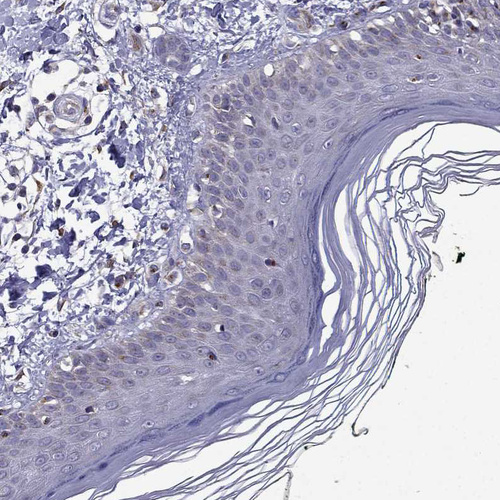

Immunohistochemical staining of human placenta shows moderate granular cytoplasmic positivity in trophoblastic cells.